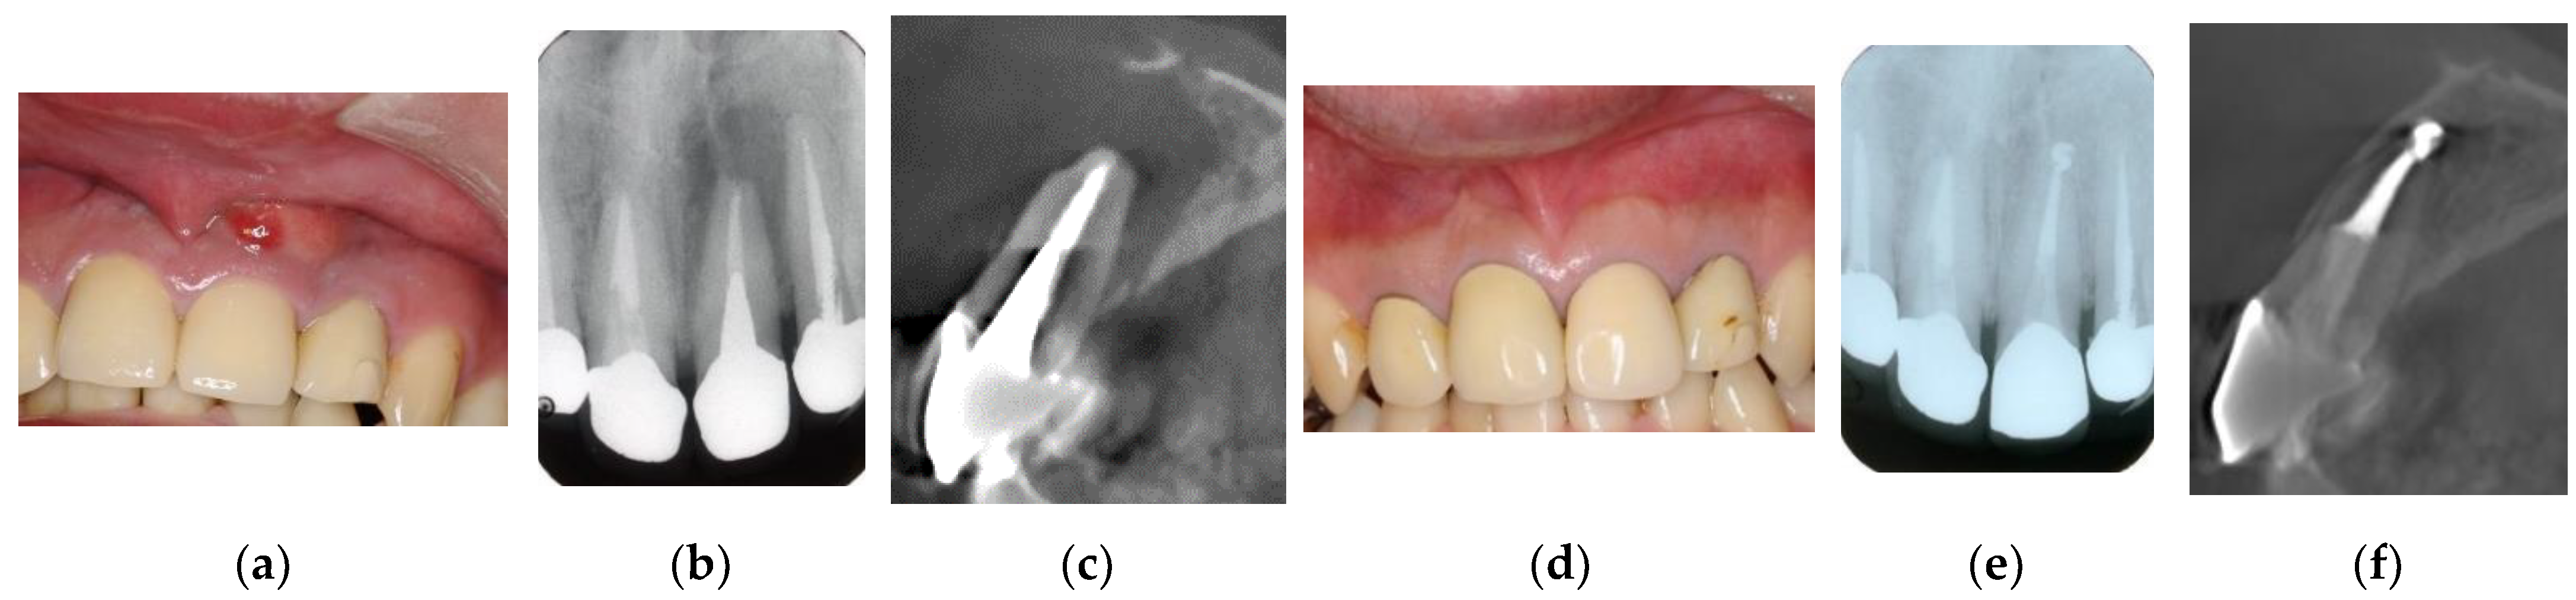

The therapeutic strategy for EPLs usually consists of initial endodontic treatment, followed, if necessary, by additional periodontal treatment, with the latter being dependent on the outcomes of endodontic treatment of the affected teeth. Periodontal defects that communicate with periapical lesions and appear to be hopelessly diseased on X-ray radiographs or CBCT may have a favorable prognosis if they are of endodontic origin (Figure 5). EPLs that are conventionally defined as untreatable on X-ray radiographs or CBCT may not be beyond treatment, as the cementum and periodontal ligaments may be intact and not affected by periapical infection and inflammatory reactions. Conventional root canal treatment is the most common therapeutic choice for periapical infections and inflammation [47,48], although its success rates in damaged roots are relatively low [29,30].

Figure 5. Clinical case 4. Male, age 34 yrs. (a) Intraoral view of the upper left incisor at baseline. (b) Preoperative periapical radiographs of the upper left incisor, with the “bone” defect presenting as a radiolucent area in the apical lesion. (c) Preoperative CBCT showing a radiolucent lesion on the labial, periapical, and palatal areas. (d) Intraoral view 2 years after treatment. (e) Follow-up periapical radiograph 2 years after treatment. (f) Follow-up CBCT 2 years after treatment, showing root canal filling and healing.